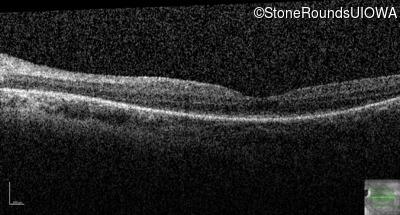

OD

OS

20/70 -2

OCT Stack

20/80 -1